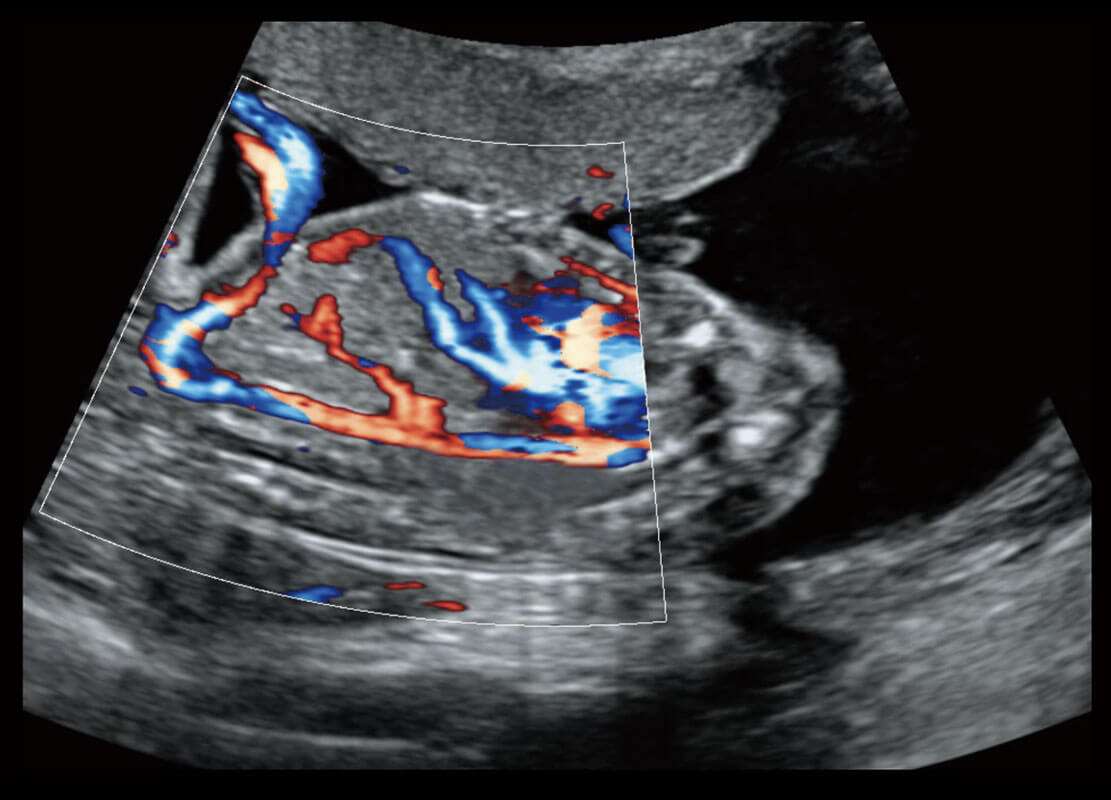

P60搭载一系列胎儿心脏成像技术,实现精细的胎儿心脏评估。

四腔切面

四腔心血流